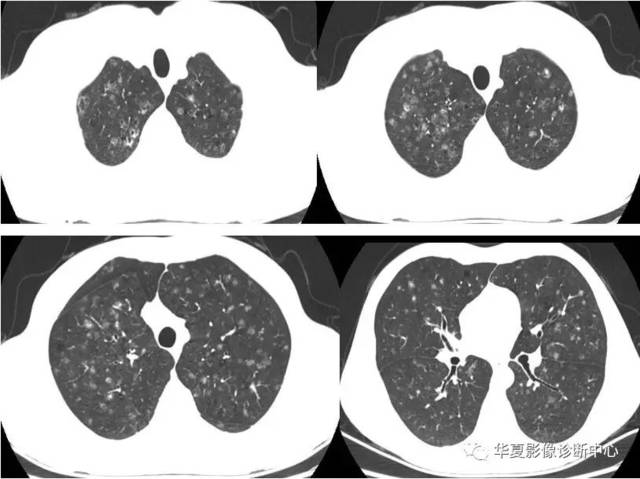

矽肺,双肺上叶大块纤维化合并小叶中央型小结节,结节边缘光整,密度较

矽肺

矽肺CT

矽肺ct图片